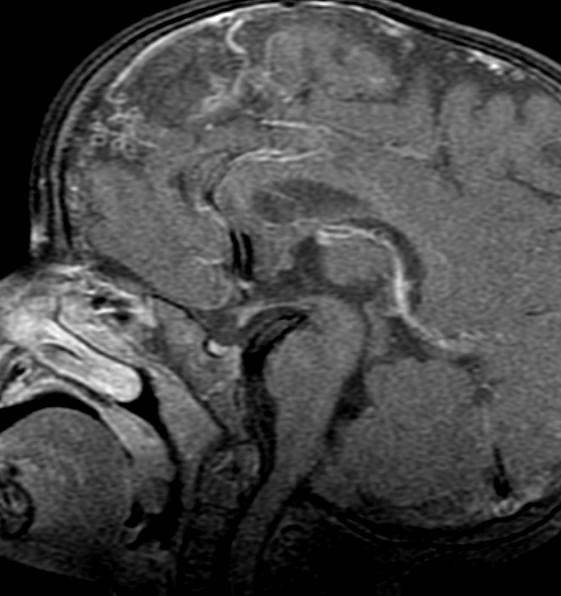

Blunted anterior Corpus, with subtle fusion at the level of the anterior commissure…?

Fusion (lack of cleavage) is just anterior /superior to the anterior commissure.